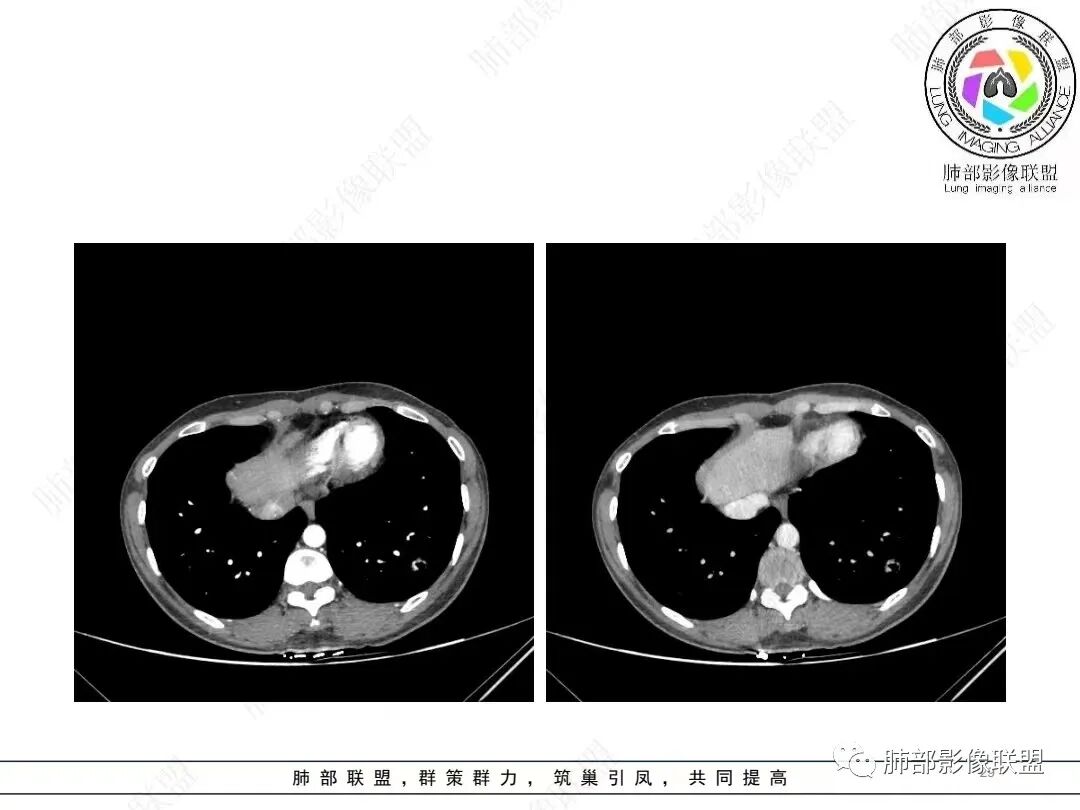

1、临床特点: 37岁女性,体检发现肺结节,2年前有甲状腺腺瘤手术史。实验室无阳性发现。

2、影像特点:左肺下叶类圆形结节影,周围可见多发细小毛刺,浅分叶,张力不高,未见胸膜牵拉。病灶内隐约见空泡影(未提供CT值),近端部分血管呈杵状增粗,可疑脐凹征。增强后实性部分有轻度强化。外围病灶,与支气管关系不明确。